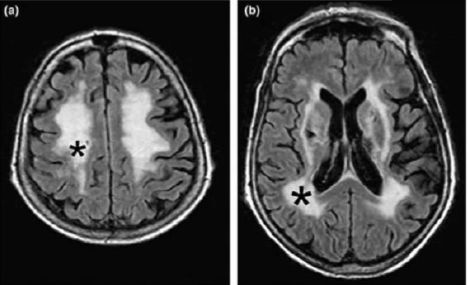

此外,该研究团队还在部分患者的脑部MRI片子上看到了服药一段时间后,脑白质区域出现了明显的异常信号(下图黑色*符号圈出了具体位置)。